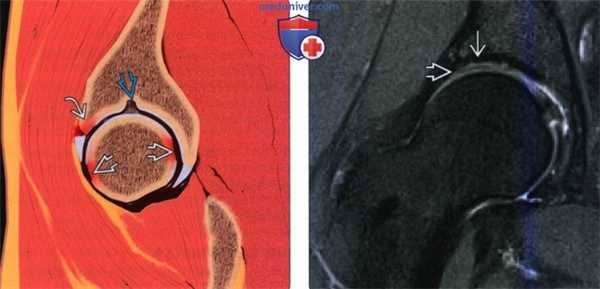

(Слева) На рисунке сагиттального среза показана травма хряща с передним разрывом губы. Типичным местом разрыва является окологубная часть вертлужной впадины. Разрывы могут возникать на головке бедренной кости, а также и на задней поверхности вертлужной впадины (удар с противоположной стороны). Обратите внимание на вариант нормы в виде надвертлужной ямки.

(Справа) МРТ, ЗТл, PDВИ, режим подавления сигнала от жира, коронарный срез: определяется травма хряща без контрастирования. Тем не менее, артефакт химического сдвига в месте травмы хряща имитирует отслойку. Использование коронарных и сагиттальных срезов подтвердит наличие этого артефакта.